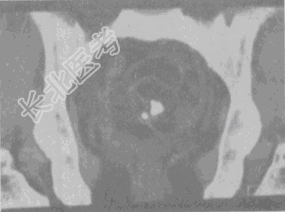

- 单项选择题女,52岁, 下腹部胀痛,B超提示盆腔占位, CT扫描如图所示,盆腔内见囊实性肿块, 其内CT值不均,从-120至300Hu不等, 最可能的诊断是

A、盆腔畸胎瘤

B、盆腔结核

C、子宫肌瘤

D、卵巢囊肿

E、卵巢黏液瘤